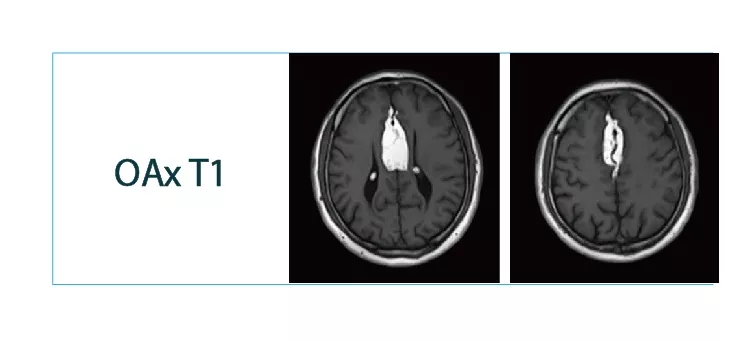

【朗润影像档案】20180511磁共振影像病例结果讨论